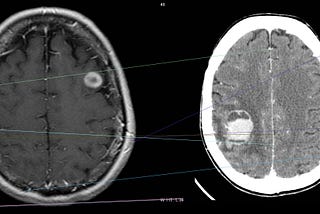

Published inAnalytics VidhyaRoboDoc , using Machine Learning to detect brain tumorsAI and medicine applicationsSep 5, 2020Sep 5, 2020